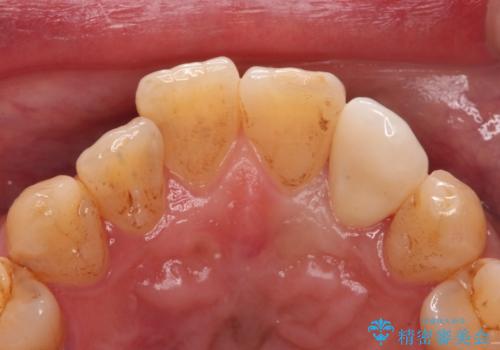

白い被せ物(ジルコニアクラウン)で治療しました。

ジルコニアクラウンについて

ジルコニアクラウンは表面がツルツルして

汚れ(細菌)や着色がつきにくいです。

ジルコニアクラウンスペシャルはジルコニアクラウンスタンダードに比べ

色のバリエーションが多く、よりご自身の天然歯の色と合うように作れます。

自然な被せ物が入り、大変満足して頂けました。